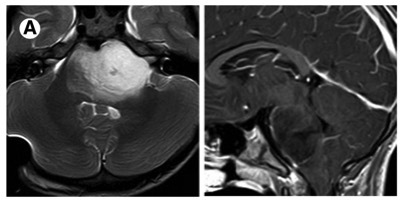

血管畸形有四种类型,动静脉畸形,海绵状血管瘤,毛细血管扩张和静脉发育性异常。实质性海绵状血管瘤MRI典型的表现为爆米花样、边界清晰、轮廓规整的复杂病变,中心区域由信号混杂灶组成,代表不同阶段的出血,其周见低信号环环绕,代表含铁血黄素沉积。

(图 A 为静脉血管瘤及海绵状血管瘤;图 B 为海绵状血管瘤(爆米花征);图 C 为毛细血管扩张;图 D 为动静脉畸形)

6、脑干发育静脉畸形:常见于20~50 岁;大多数无症状,有时与癫痫、头痛、神经功能缺损或脑积水相关,但很少出现破裂或出血。典型影像学表现:海蛇头。

7、脑干海绵状血管瘤:一次发病多在 30 岁左右,易出血(每年增加 2.4%~6%)及再出血(21%~60%),典型影像学表现:「桑葚样」或「爆米花样」。

8、脑干毛细血管扩张:大多数无症状,是否与临床表现相关不明确;病灶大部分位于脑桥,单一,小病灶(通常小于 2 cm),大多数在 T1 相正常,T2WI 等信号或稍高信号,均匀强化或点缀样强化;强化灶边界不规则,刷样改变,而并无特异性;特征性影像学表现为 T2*GE 序列毛细血管扩张。其它影像学表现包括:无占位效应,随访病灶稳定。

9、脑干动静脉畸形:原发性脑内动静脉畸形少见,常见20~30 岁,易出血,80%~90% 的患者因颅内出血而就诊,在脑干部位好发中脑,其次为脑桥及延髓;脑干部位 AVM 与颅内 AVM 影像学表现一致;异常扩张、发育血管结构,「流空」现象,有时因血管内高流速或血栓形成可呈高信号,AVM 破裂时可有出血征象。